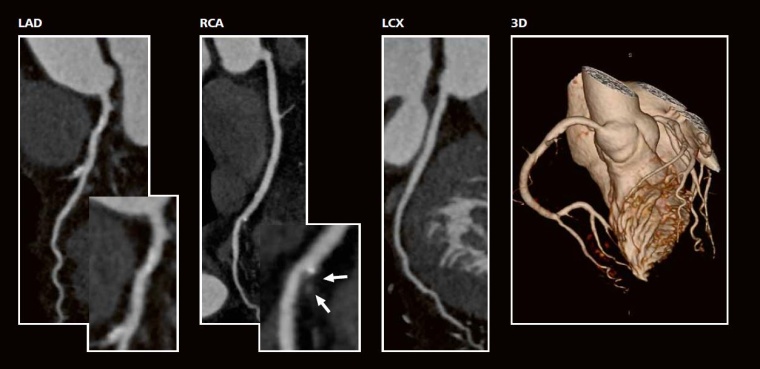

Fall 1

Anamnese:

77-jährige Dame, Aufnahme wg. paroxysmalem Vorhofflimmern, Herzfrequenz (HF): 141 bpm. Spontankardioversion in einen normfrequenten Sinusrhythmus (HF: 65 bpm). Atypische Angina Pectoris. In der Fahrrad-Ergometrie Schwindel, Übelkeit und Blutdruckabfall.

Kardiovaskuläre Risikofaktoren:

arterielle Hypertonie, unter Therapie (Diuretikum, ACE-Hemmer, Beta-Blocker) Blutdruck in Ruhe: 115/60 mmHg, prä-Diabetes, Nichtraucherin, LDL-Cholesterin: < 70 mg/dl, negative Familienanamnese. Framingham Risiko Score (FRS) = 5 % Herzinfarktrisiko in den nächsten 10 Jahren (= niedriges Risiko).

CT -Angiographie:

in der multiplanaren Rekonstruktion (Curved MPR) diskrete kalzifizierte und nicht-kalzifizierte Plaquebildung im proximalen RIVA (links), Ramus Diagonalis 1 (links) und in der mittleren RCA (Mitte, weiße Pfeile). Unauffällige LCX (rechts). Gesamt-Agatston-Score = 290 (mittleres Risiko). Keine relevanten Stenosen (3D-Bild). Strahlendosis CTA = 0,7 mSv.

Therapie:

Optimierung der kardiovaskulären Risikofaktoren, insbesondere der prä-diabetischen Stoffwechsellage.